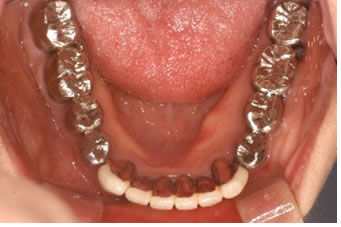

症例1

治療の特徴(患者T様)

平成13年7月7日 右下第一大臼歯頬側に膿瘍形成 著しい腫れ形成 著しい腫れ

- 男性33歳

- 平成14年11月9日 どうしても抜きたくないということで歯周外科処置する。

- その後H16から1~2カ月おきにメインテナンス。

- 平成16年6月11日 歯周治療により骨が出来てきています。

口の中から細菌を除去し、良好な環境を維持していくことによって歯周組織である歯槽骨や歯肉、歯根膜は生き生きとよみがえってきます。継続は力なりと申しますが根気良く治療を続けることで健康が回復し維持されます。

| 歯周外科に対するデメリット | 外科処置ですので麻酔が必要な処置である。全身疾患がある場合には先に体調管理を行う必要がある。処置後1週間ぐらいは治療部位のブラッシングが出来ない。冷たいものがしみることがある。 |

|---|---|

| 治療期間 | 4年7カ月 |